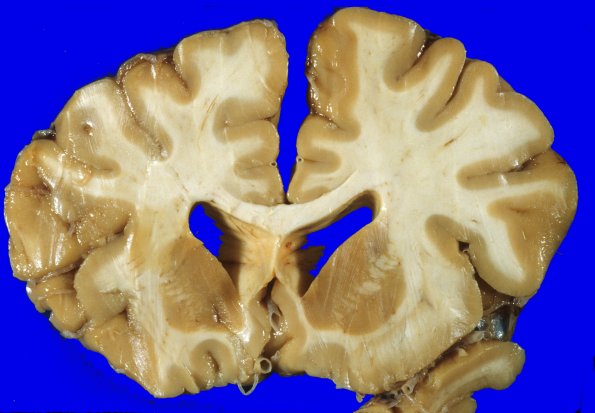

At autopsy the brain was unfortunately not weighed. There is modest atrophy of the cerebral hemispheres and dilatation and blunting of the lateral ventricles.